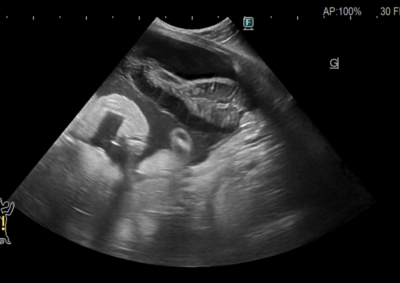

軟部組織外科 注意 ボタンをクリックした先に、治療中および手術中の画像が説明で使用されている場合がございます。 そのような画像に弱い方は閲覧なさらないようお願いいたします。 軟部組織外科救急・集中治療 胆嚢粘液嚢腫破裂 軟部組織外科腫瘍外科 膵臓腫瘍による肝外胆管閉塞 軟部組織外科救急・集中治療 肝葉捻転 軟部組織外科救急・集中治療 尿道腫瘍・膀胱瘻チューブ設置 軟部組織外科 経恥骨骨切り尿道瘻設置術 救急・集中治療軟部組織外科 猫の子宮蓄膿症 軟部組織外科 猫の直腸脱 軟部組織外科救急・集中治療 猫の腸閉塞(毛玉) 軟部組織外科救急・集中治療 小腸腫瘍壊死による細菌性腹膜炎 軟部組織外科救急・集中治療 異物による十二指腸穿孔・細菌性腹膜炎 軟部組織外科 腸閉塞・腸切開 軟部組織外科救急・集中治療 犬の胆嚢粘液嚢腫破裂 <123456789> 症例カテゴリー 放射線治療整形外科軟部組織外科脳神経外科内科腫瘍外科救急・集中治療リハビリテーション科腫瘍内科内視鏡科脳神経科呼吸器外科中医・漢方猫の腎移植循環器科